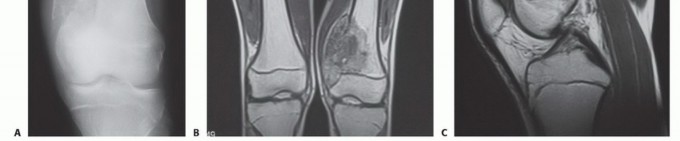

Sarcomas typically form a solid, expansile mass that grows centrifugally. Due to this centrifugal growth pattern, the periphery of the lesion is the least mature, most cellular, and most biologically active region, making it the ideal target for biopsy sampling. Unlike the true capsule that surrounds benign lesions—which is composed of compressed normal cells and mature fibrous tissue—sarcomas are generally enclosed by a reactive zone commonly referred to as a "pseudocapsule."

This pseudocapsule consists of compressed tumor cells, a fibrovascular zone of reactive tissue, and a variable inflammatory component that interacts with the surrounding normal tissues. Crucially, the pseudocapsule is not a true anatomic barrier. Microscopic tumor extensions, known as satellite lesions, frequently penetrate this reactive zone and reside in the immediately adjacent normal-appearing tissue. Therefore, a biopsy that breaches the pseudocapsule inevitably contaminates the surrounding tissue planes with malignant cells.

Imaging and Staging

Prior to any tissue sampling, complete local and systemic imaging must be obtained. This typically includes high-quality orthogonal plain radiographs of the affected bone, and a contrast-enhanced MRI of the entire anatomic compartment (joint-to-joint) to assess tumor volume, neurovascular proximity, and the presence of skip metastases. Staging studies, including a CT of the chest to rule out pulmonary metastases, and potentially a whole-body bone scan or PET-CT, should be completed or scheduled prior to the biopsy.

- Sampling: The sample must be taken from the periphery of the tumor (the most viable tissue), avoiding the necrotic center. Frozen section should be utilized to confirm that diagnostic tissue (not just necrotic debris) has been obtained.